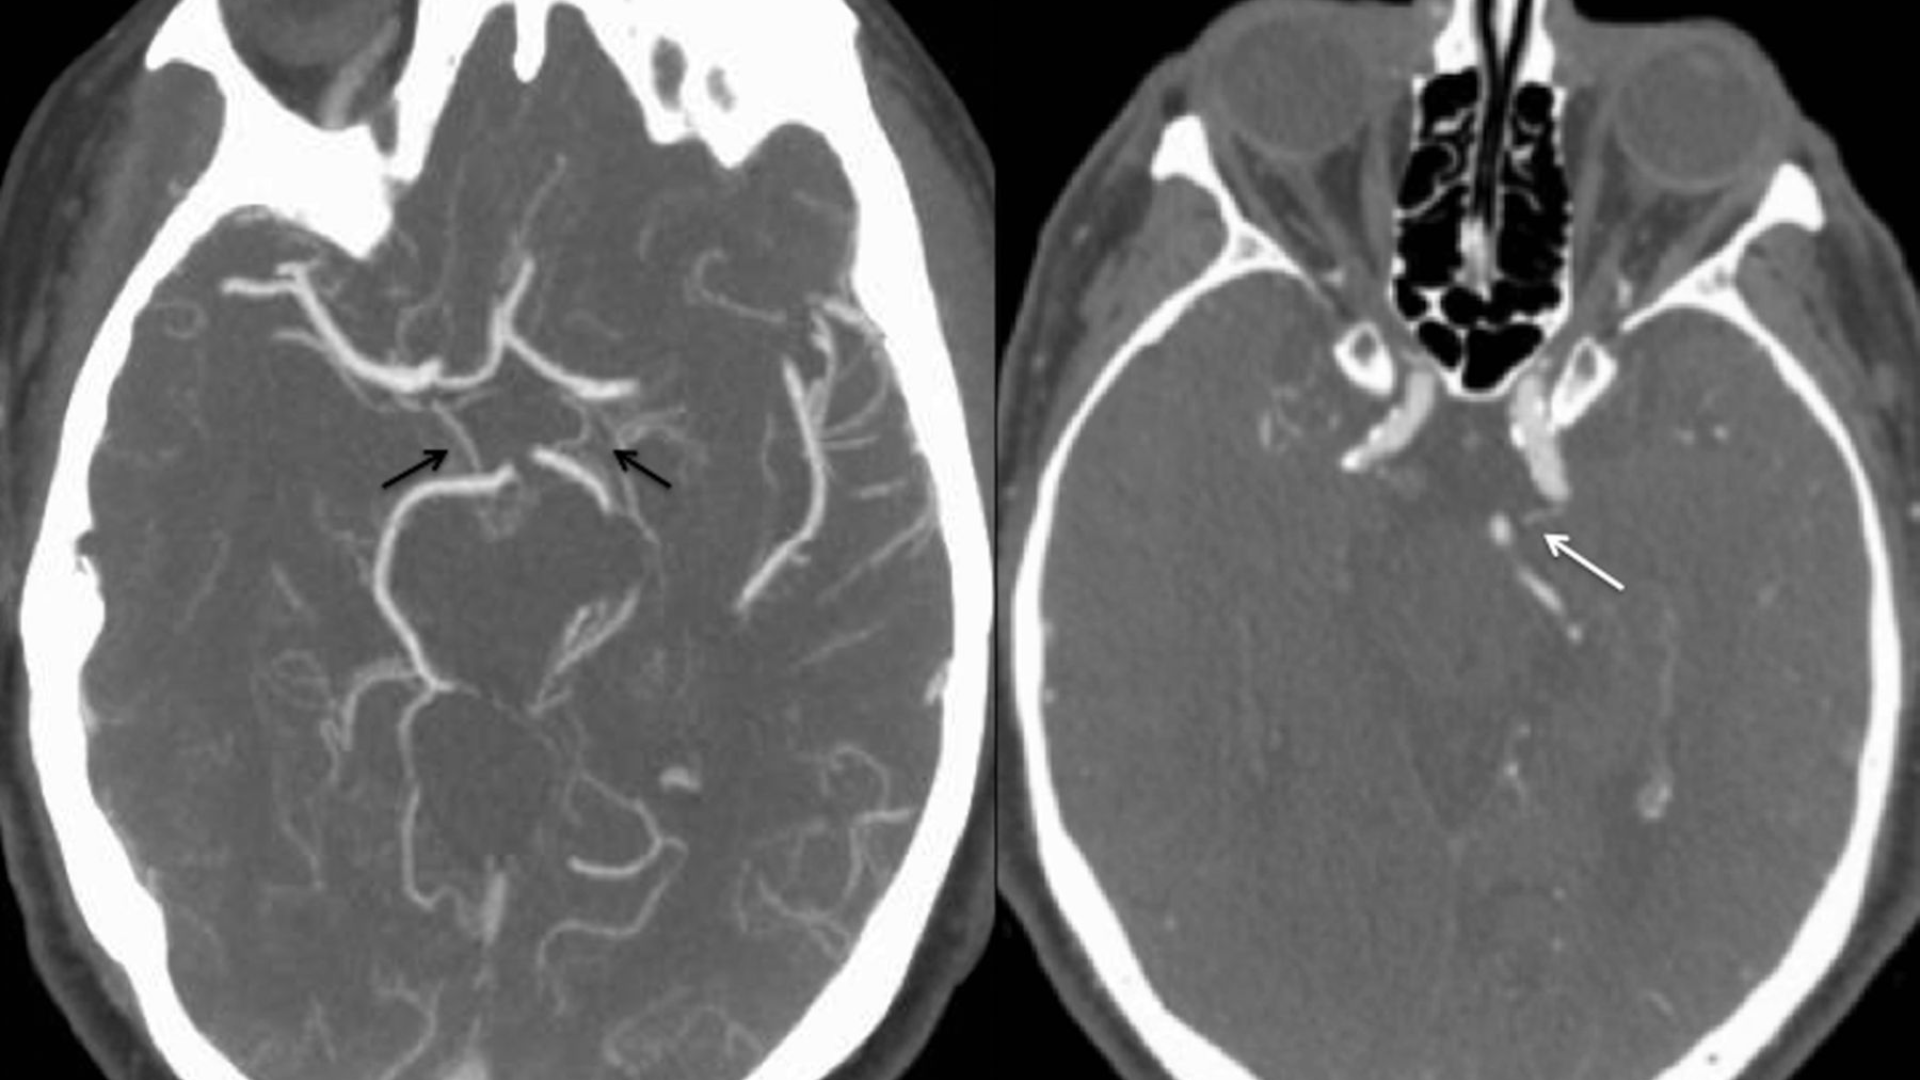

CT mạch máu não giúp phát hiện túi phình mạch não, đánh giá chính xác kích thước, hình dạng và vị trí phình mạch. Đây là bệnh lý nguy hiểm vì phình mạch có nguy cơ vỡ gây xuất huyết não đột ngột, đe dọa tính mạng nếu không được phát hiện và xử trí kịp thời.

Phương pháp này cho phép đánh giá mức độ hẹp hoặc tắc các động mạch não do xơ vữa, huyết khối hoặc co thắt mạch. Thông tin này rất quan trọng trong tiên lượng nguy cơ đột quỵ thiếu máu não và lựa chọn chiến lược điều trị phù hợp.

CT mạch máu não có thể phát hiện dị dạng động - tĩnh mạch não, giúp đánh giá cấu trúc bất thường của mạch máu, mức độ shunt và ảnh hưởng đến mô não xung quanh.

Trong cấp cứu đột quỵ, CT mạch máu não giúp xác định nhanh vị trí tắc mạch lớn, mức độ tổn thương và khả năng can thiệp tái thông mạch, hỗ trợ bác sĩ đưa ra quyết định điều trị kịp thời.